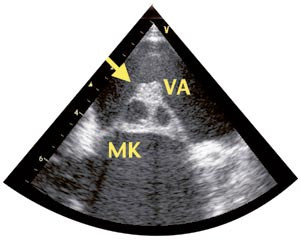

Transtorakal og transøsofageal ekkokardiografi viste bikuspid aortaklaff med lekkasje av moderat grad. Venstre ventrikkel var noe utvidet med god pumpefunksjon. På atriesiden av fremre mitralseil ble det påvist en tumorliknende oppfylling. Sentralt i denne oppfyllingen var det to hulrom. Høyre hjertehalvdel var normal.

EKG, røntgen thorax og ultralydundersøkelse av lever, galle, pancreas og nyrer gav normale resultater. Røntgen av kjevene viste rotabscess, og en tann ble fjernet. MR av hjernen viste flere mindre lesjoner, tolket som infarkter. Transtorakal og transøsofageal ekkokardiografi bekreftet at aortaklaffen var bikuspid. Aortalekkasjen ble vurdert som stor. Det var en normalt fungerende mitralklaff med en oppfylling på atriesiden av fremre seil med to hulrom og en påleiring på toppen (fig 1). Det kunne ikke utelukkes at det var blodstrøm inne i hulrommene (fig 2). Det ble også påvist en innbukning i aortaroten som gav mistanke om et abscesshulrom (fig 3). MR av hjertet bekreftet funnene, men gav ingen ytterligere opplysninger.

Vår pasient hadde en oppfylling på fremre mitralseil som først og fremst ble oppfattet som en vegetasjon. Usikkerheten berodde på at oppfyllingen ikke hadde en oscillerende karakter som er typisk for vegetasjoner. Derfor ble også andre differensialdiagnoser som myksom og fibroelastom vurdert. Hulrommene i vegetasjonen ble umiddelbart mistenkt for å være abscesser (fig 1). Imidlertid bør man skille mellom ekte abscesser og abscesshulrom. Ekte abscesser kan være vanskelige å oppdage ved ekkokardiografi siden de inneholder puss og derfor gir samme ekko som myokard. De forekommer mye sjeldnere enn abscesshulrom og medfører sannsynligvis dårligere prognose, muligens på grunn av manglende blodforsyning med vanskelig tilgjengelighet for antibiotika.

Abscesshulrom kan tenkes å være pseudoaneurismer, forårsaket av en kombinasjon av infeksjon og hemodynamiske forhold. Bakgrunnen for denne hypotesen er at slike hulrom sjelden forekommer i lavtrykkskamre, som venstre atrium og høyre hjertehalvdel. Hos vår pasient bør hulrommet i aortaroten og hulrommene i «vegetasjonen» betegnes som abscesshulrom og ikke som abscesser, siden det ikke var tegn til puss.